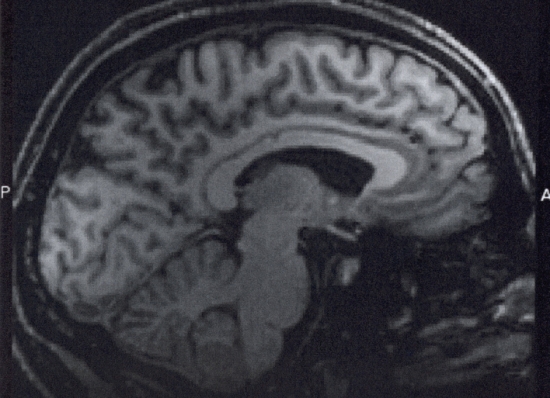

The glucose metabolism of the brain of an Alzheimer’s patient is diminished in the area believed to deal with memory. The patients in the pilot study showed a slight increase of glucose consumption in that region of the brain.

The new study will implant DBS devices that will either be active or inactive into patients, who through brain scans and doctor’s observations, will be studied for a year. The hypothesis is that the electrical activity caused by the device could stimulate critical parts of the brain. They hope this could slow or reduce the atrophy of brain tissue associated with the disease.